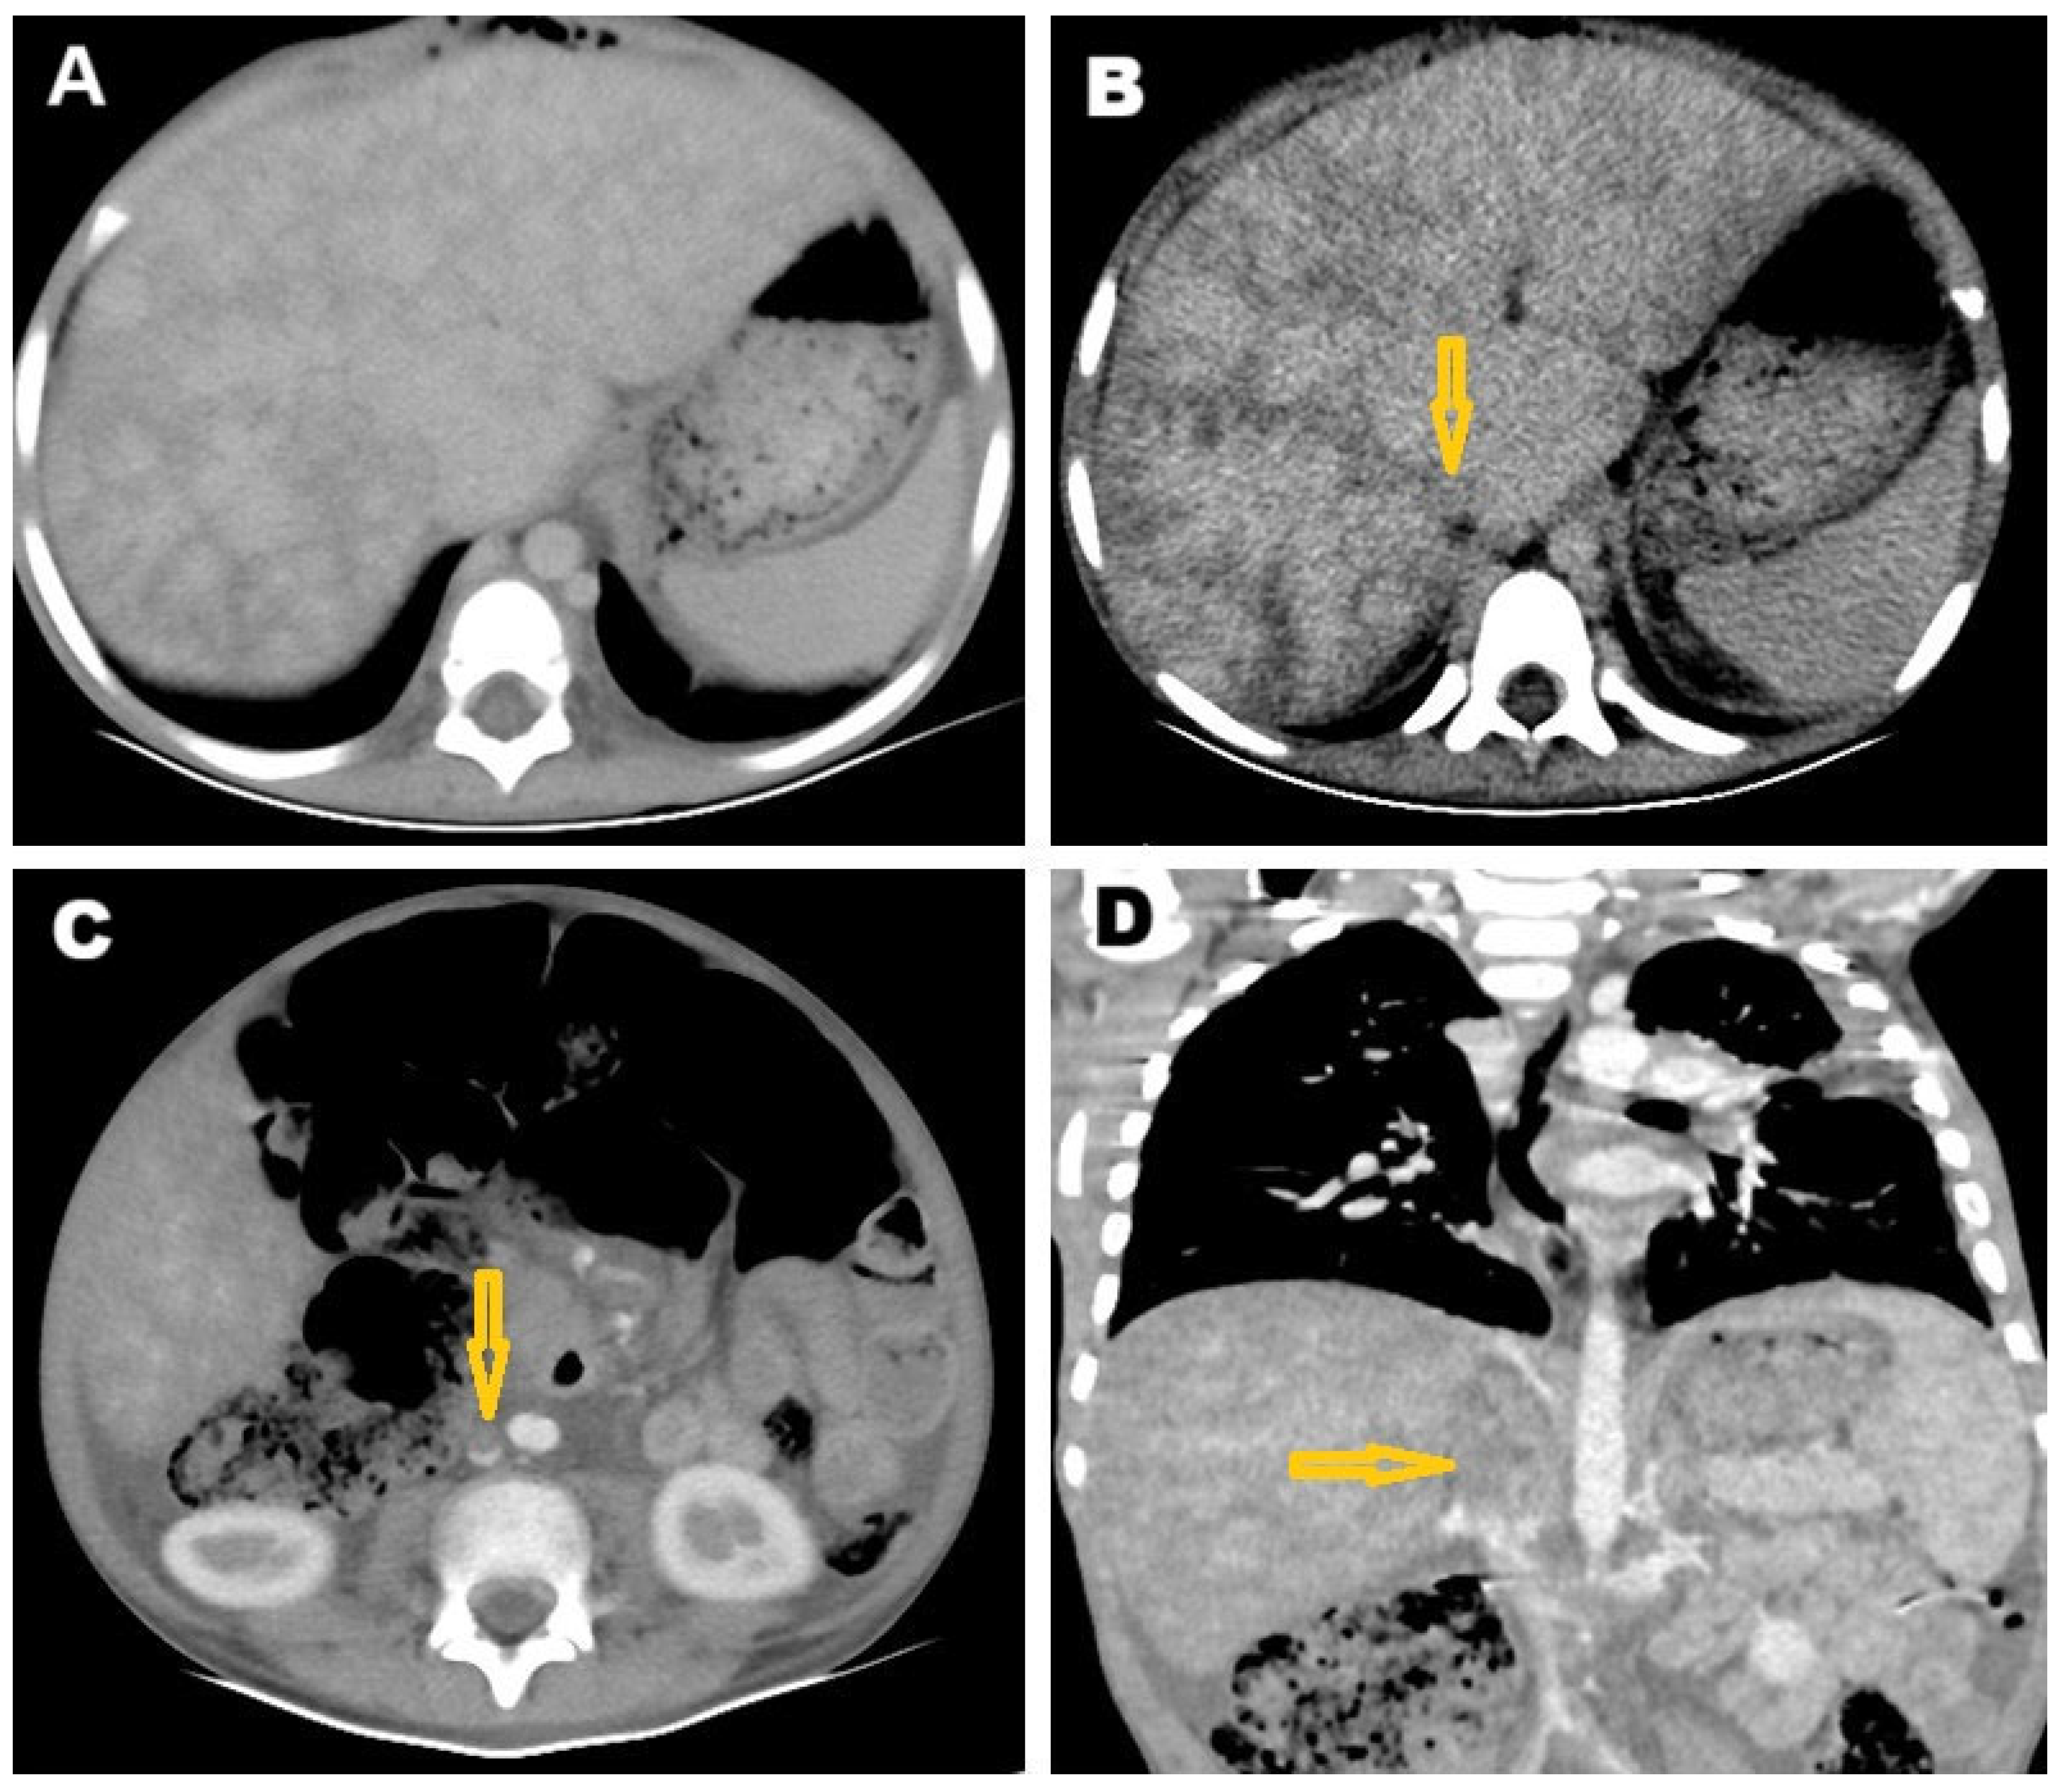

2. Case Presentation